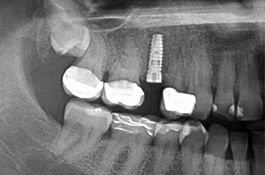

Als Implantat bezeichnet man in der Zahnmedizin eine künstliche Zahnwurzel, die nach Verlust eines eigenen Zahnes als Ersatz eingebracht wird. Das Implantat dient als Basis bzw. Verankerung einer festsitzenden Krone. Geht nur ein Zahn verloren, dient das Implantat zum Schluss der Lücke, ohne dass eine Brücke angefertigt werden muss und dafür die vielleicht intakten Nachbarzähne abgeschliffen werden. Damit schonen wir die umgebenden Zähne. Spätfolgen des Zahnverlustes, wie Kiefergelenkprobleme, Zahnwanderungen oder Karies können vermieden werden. Sind bereits mehrere Zähne verloren gegangen, die nur durch eine Teil- oder Vollprothese ersetzt werden können, ermöglichen wir durch das Einbringen mehrerer Implantate wieder einen festsitzenden Zahnersatz.

Implantate bestehen aus dem körperverträglichen und langlebigen Metall Titan. In einem minimalinvasiven operativen Eingriff setzen wir das Implantat in den Knochen ein. Die speziell bearbeitete Oberfläche garantiert ein zügiges Einheilen und das feste Verwachsen mit dem umgebenden Knochengewebe. Implantate können darüber hinaus den gefürchteten Knochenschwund in zahnlosen Kieferabschnitten verhindern oder verzögern. Den eigenen Zahnwurzeln ähnlich, übertragen Implantate die Kaukräfte auf den Kieferknochen. Dieser Trainingseffekt ist ein wichtiger Reiz für den Erhalt des Knochen- und Stützgewebes. Deshalb sollten Implantate möglichst bald nach dem Verlust oder Entfernen eines Zahns verankert werden.